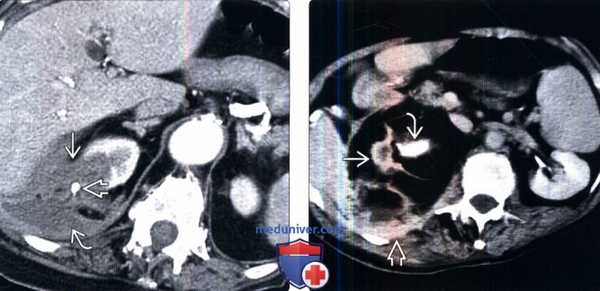

(Слева) КТ с контрастированием, аксиальная проекция: неконтрастируемое объемное образование низкой плотности в верхнем полюсе правой почки, ассоциированное с кальцификацией и околопочечными воспалительными изменениями, а также абсцессом. Визуализированные признаки возможны при очаговом ксантогранулематозном пиелонефрите.

(Справа) КТ с контрастированием, аксиальная проекция: крупный конкремент в лоханке правой почки и атрофия почки. Обратите внимание на липидную пролиферацию, окружающую почку, и распространение воспалительного процесса на забрюшинное пространство и мышцы спины.